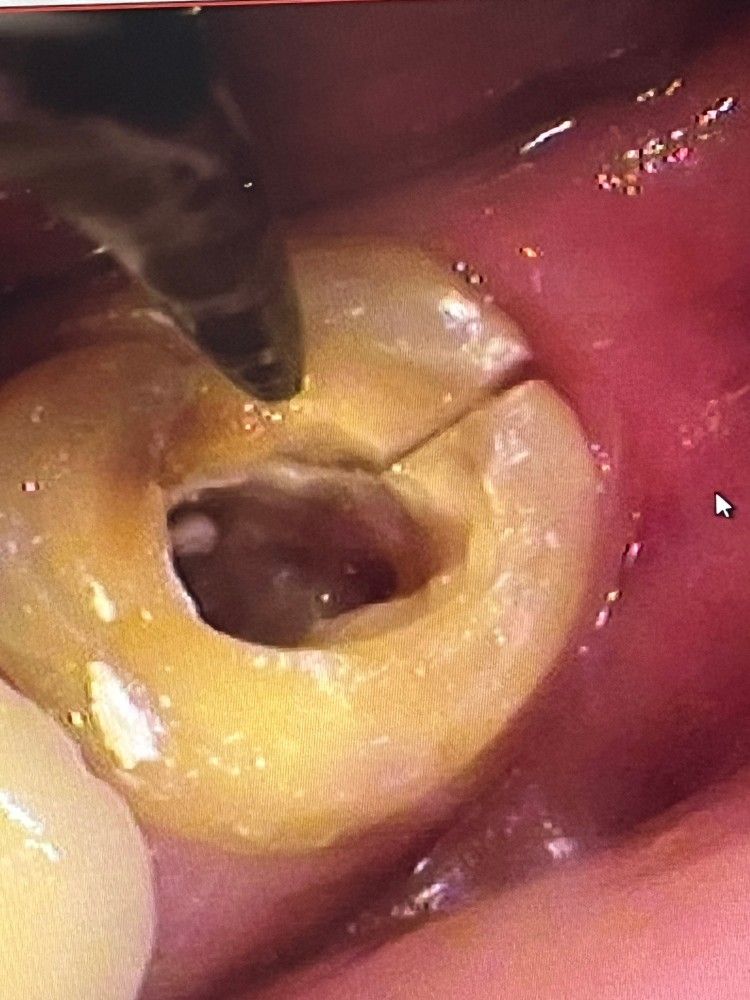

첫번째 사진이 원래 금이 가있던 부분을 동그라미 친 사진입니다

두번째 사진은 누가봐도 금이 선명해서 표시를 안했지만 잘 보시면 금이 3개 가있습니다

• 1번 째 사진

• 2번 째 사진